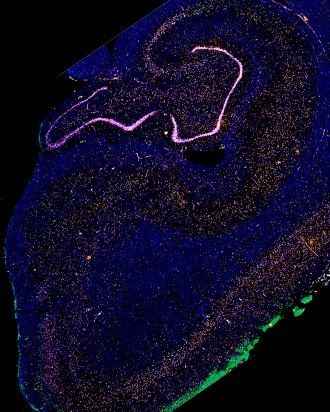

En una primera fase, el equipo investigador dirigido por Kun Leng y Emmi Li, co-primeros autores del estudio, estudió tejido de 10 cerebros de donantes utilizando la técnica secuenciación de ARN de un solo núcleo, que permite agrupar las neuronas basadas en patrones de actividad génica. En una región cerebral llamada corteza entorhinal, una de las primeras áreas atacadas por la enfermedad de Alzheimer, los investigadores identificaron un subconjunto particular de neuronas que comenzaron a desaparecer muy temprano en la enfermedad. Más tarde, en el curso de la enfermedad, los investigadores encontraron, un grupo similar de neuronas también fueron los primeros en morir cuando la degeneración llegó al giro frontal superior del cerebro.

En ambas regiones, estas células vulnerables se distinguieron por su expresión de una proteína llamada RORB. Esto permitió a los investigadores del laboratorio de neuropatología de Grinberg, dirigido por el ex gerente de laboratorio Rana Eser, examinar las neuronas que expresan RORB con más detalle en el tejido cerebral de una cohorte más grande de 26 donantes.

Utilizaron técnicas de tinción histológica para examinar el destino de las células tanto de individuos sanos como de aquellos con Alzheimer en etapa temprana y tardía. Este trabajo validó que las neuronas que expresan RORB mueren de hecho al principio de la enfermedad y también acumulan enredos tau antes que las neuronas vecinas que no expresan RORB.